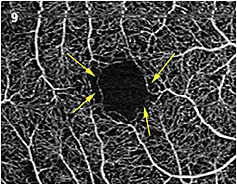

- Early changes in diabetic retinopathy. Patients with diabetes are advised to have a dilated eye exam on an annual basis. Without any evidence of hemorrhage or edema, these patients typically aren’t evaluated with angiography. OCTA may be useful to identify early changes in the parafoveal capillaries before typical changes are seen (Figure 9). These smaller capillaries may be some of the first to have impaired perfusion and can be part of a loss of the greater capillary bed. It is prudent to state that we have yet to establish a normative parafoveal capillary database, so any abnormalities seen may be a normal variant. The only way to be sure if the vessels are damaged is to establish a baseline for the individual patient then follow up with OCTA to identify changes.